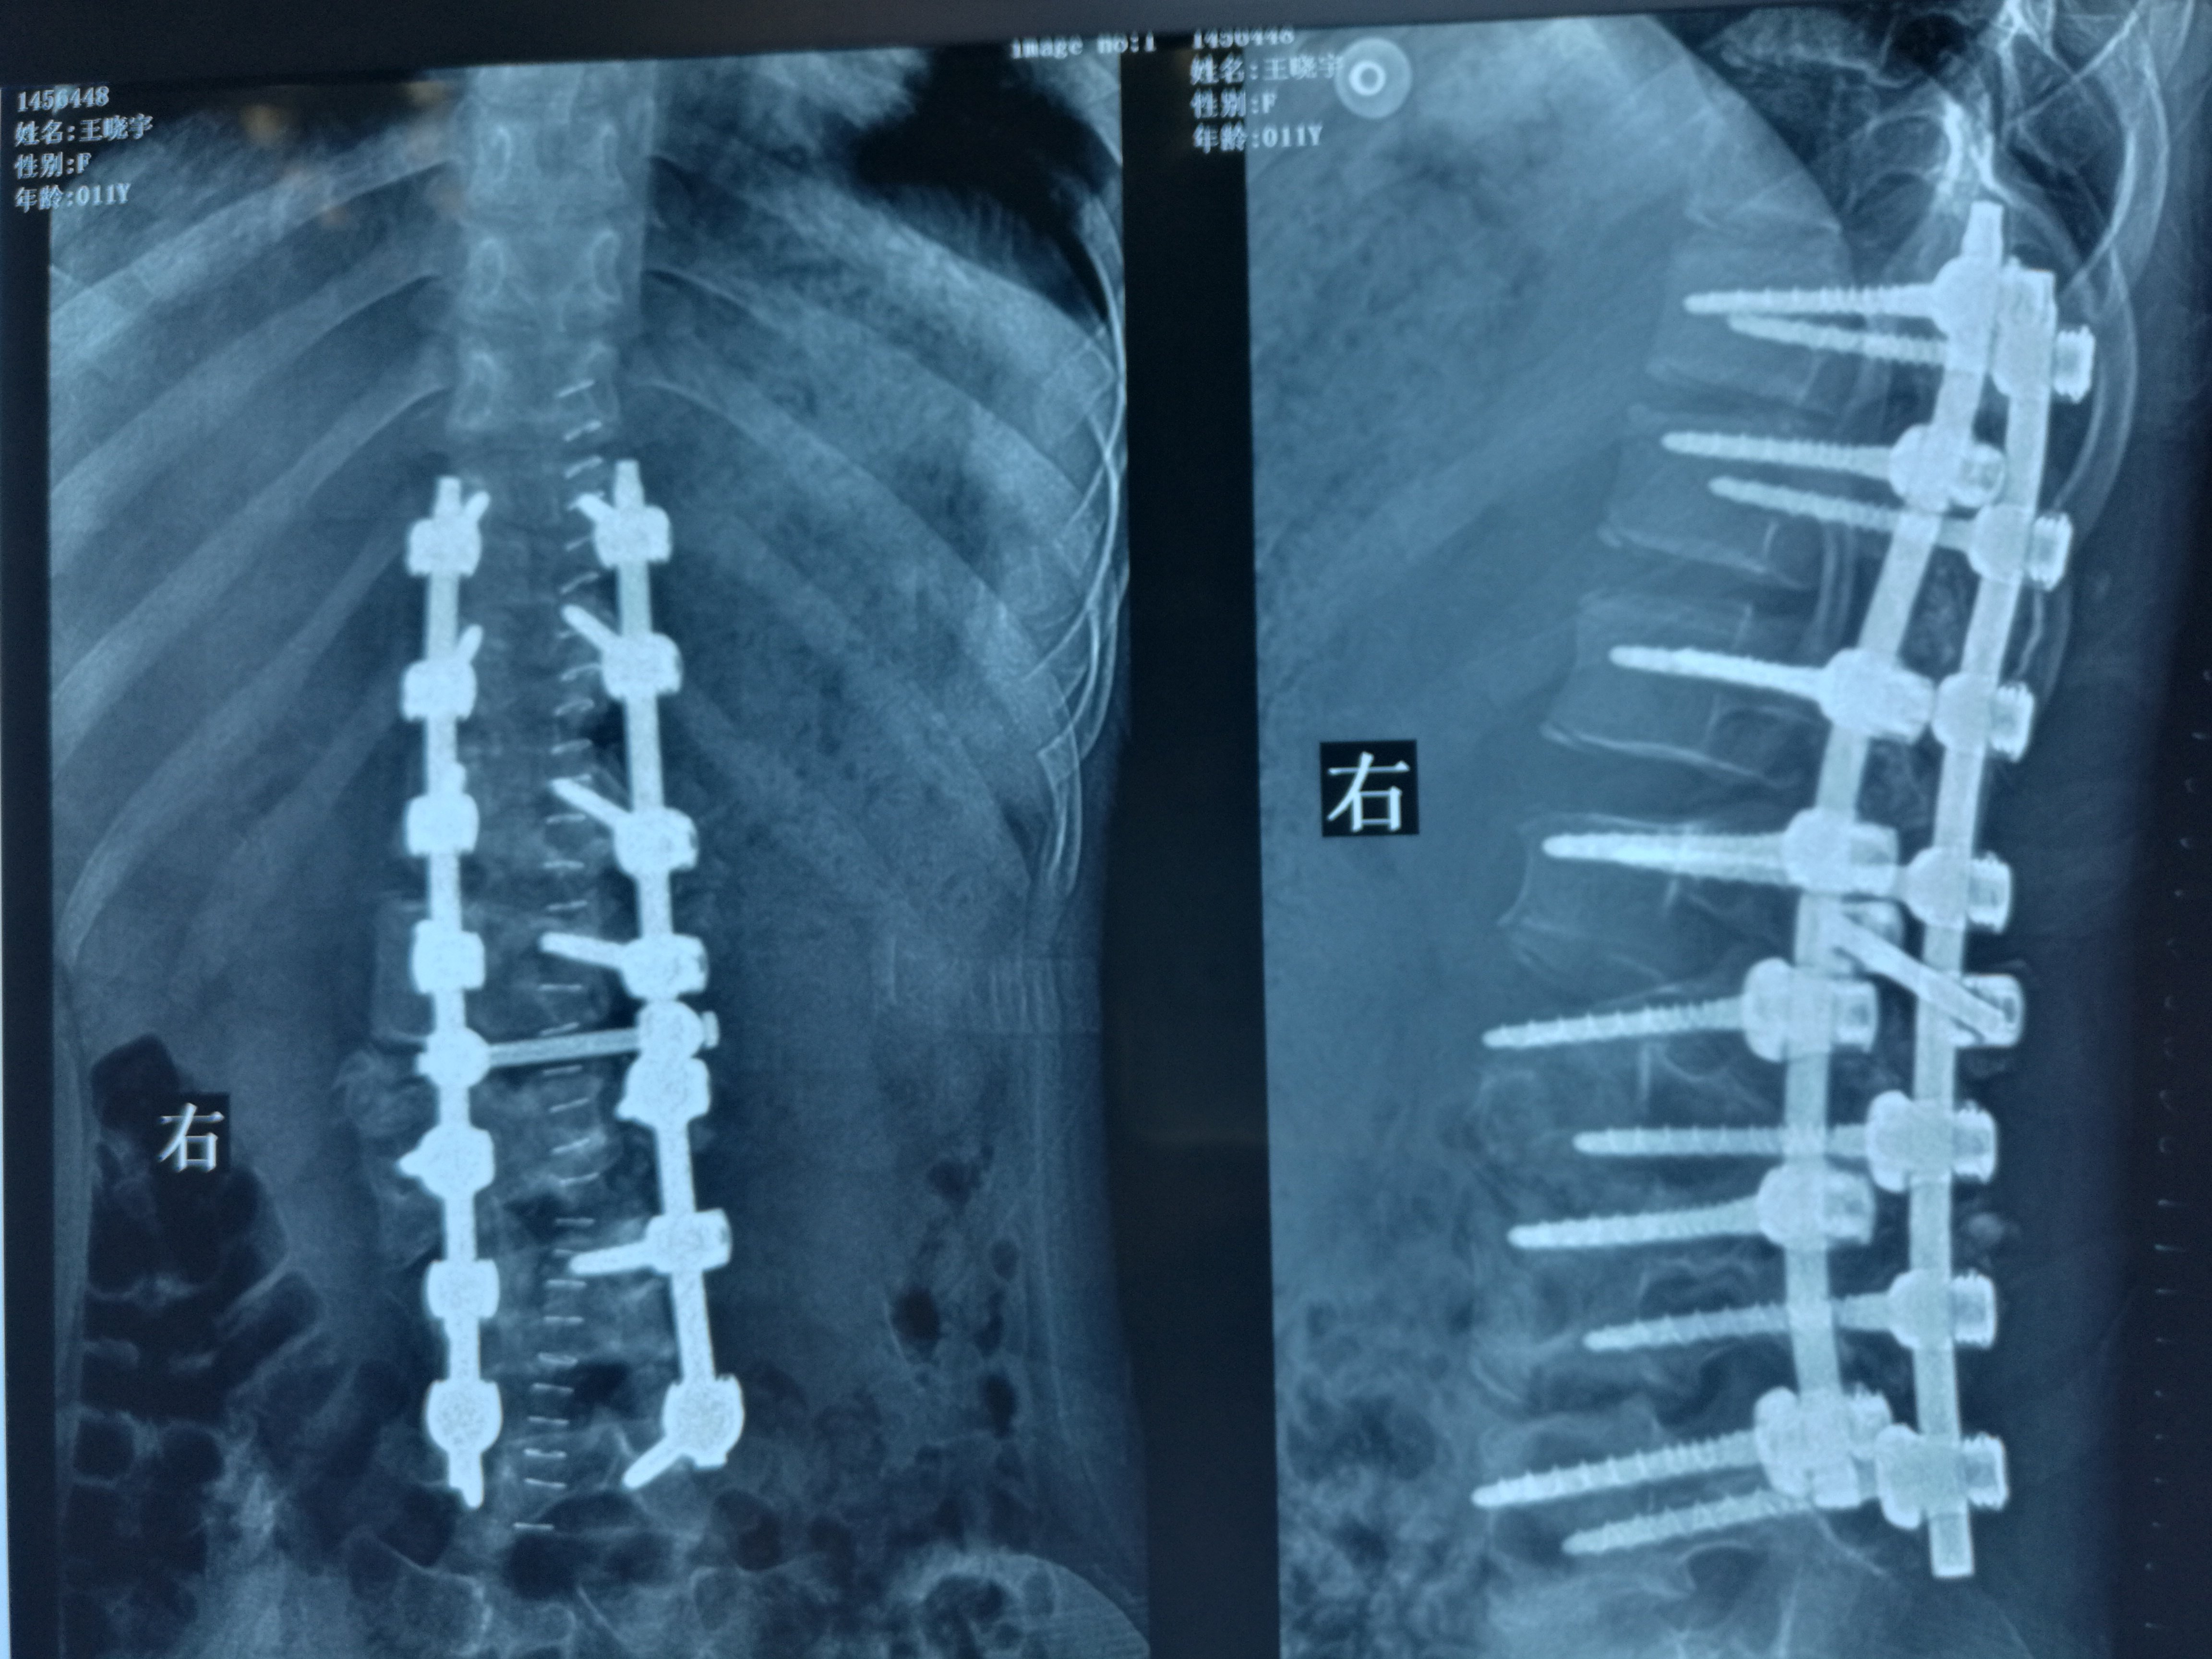

脊柱侧弯 术中影像

重度脊柱侧弯矫正手术实例二

脊柱侧弯手术